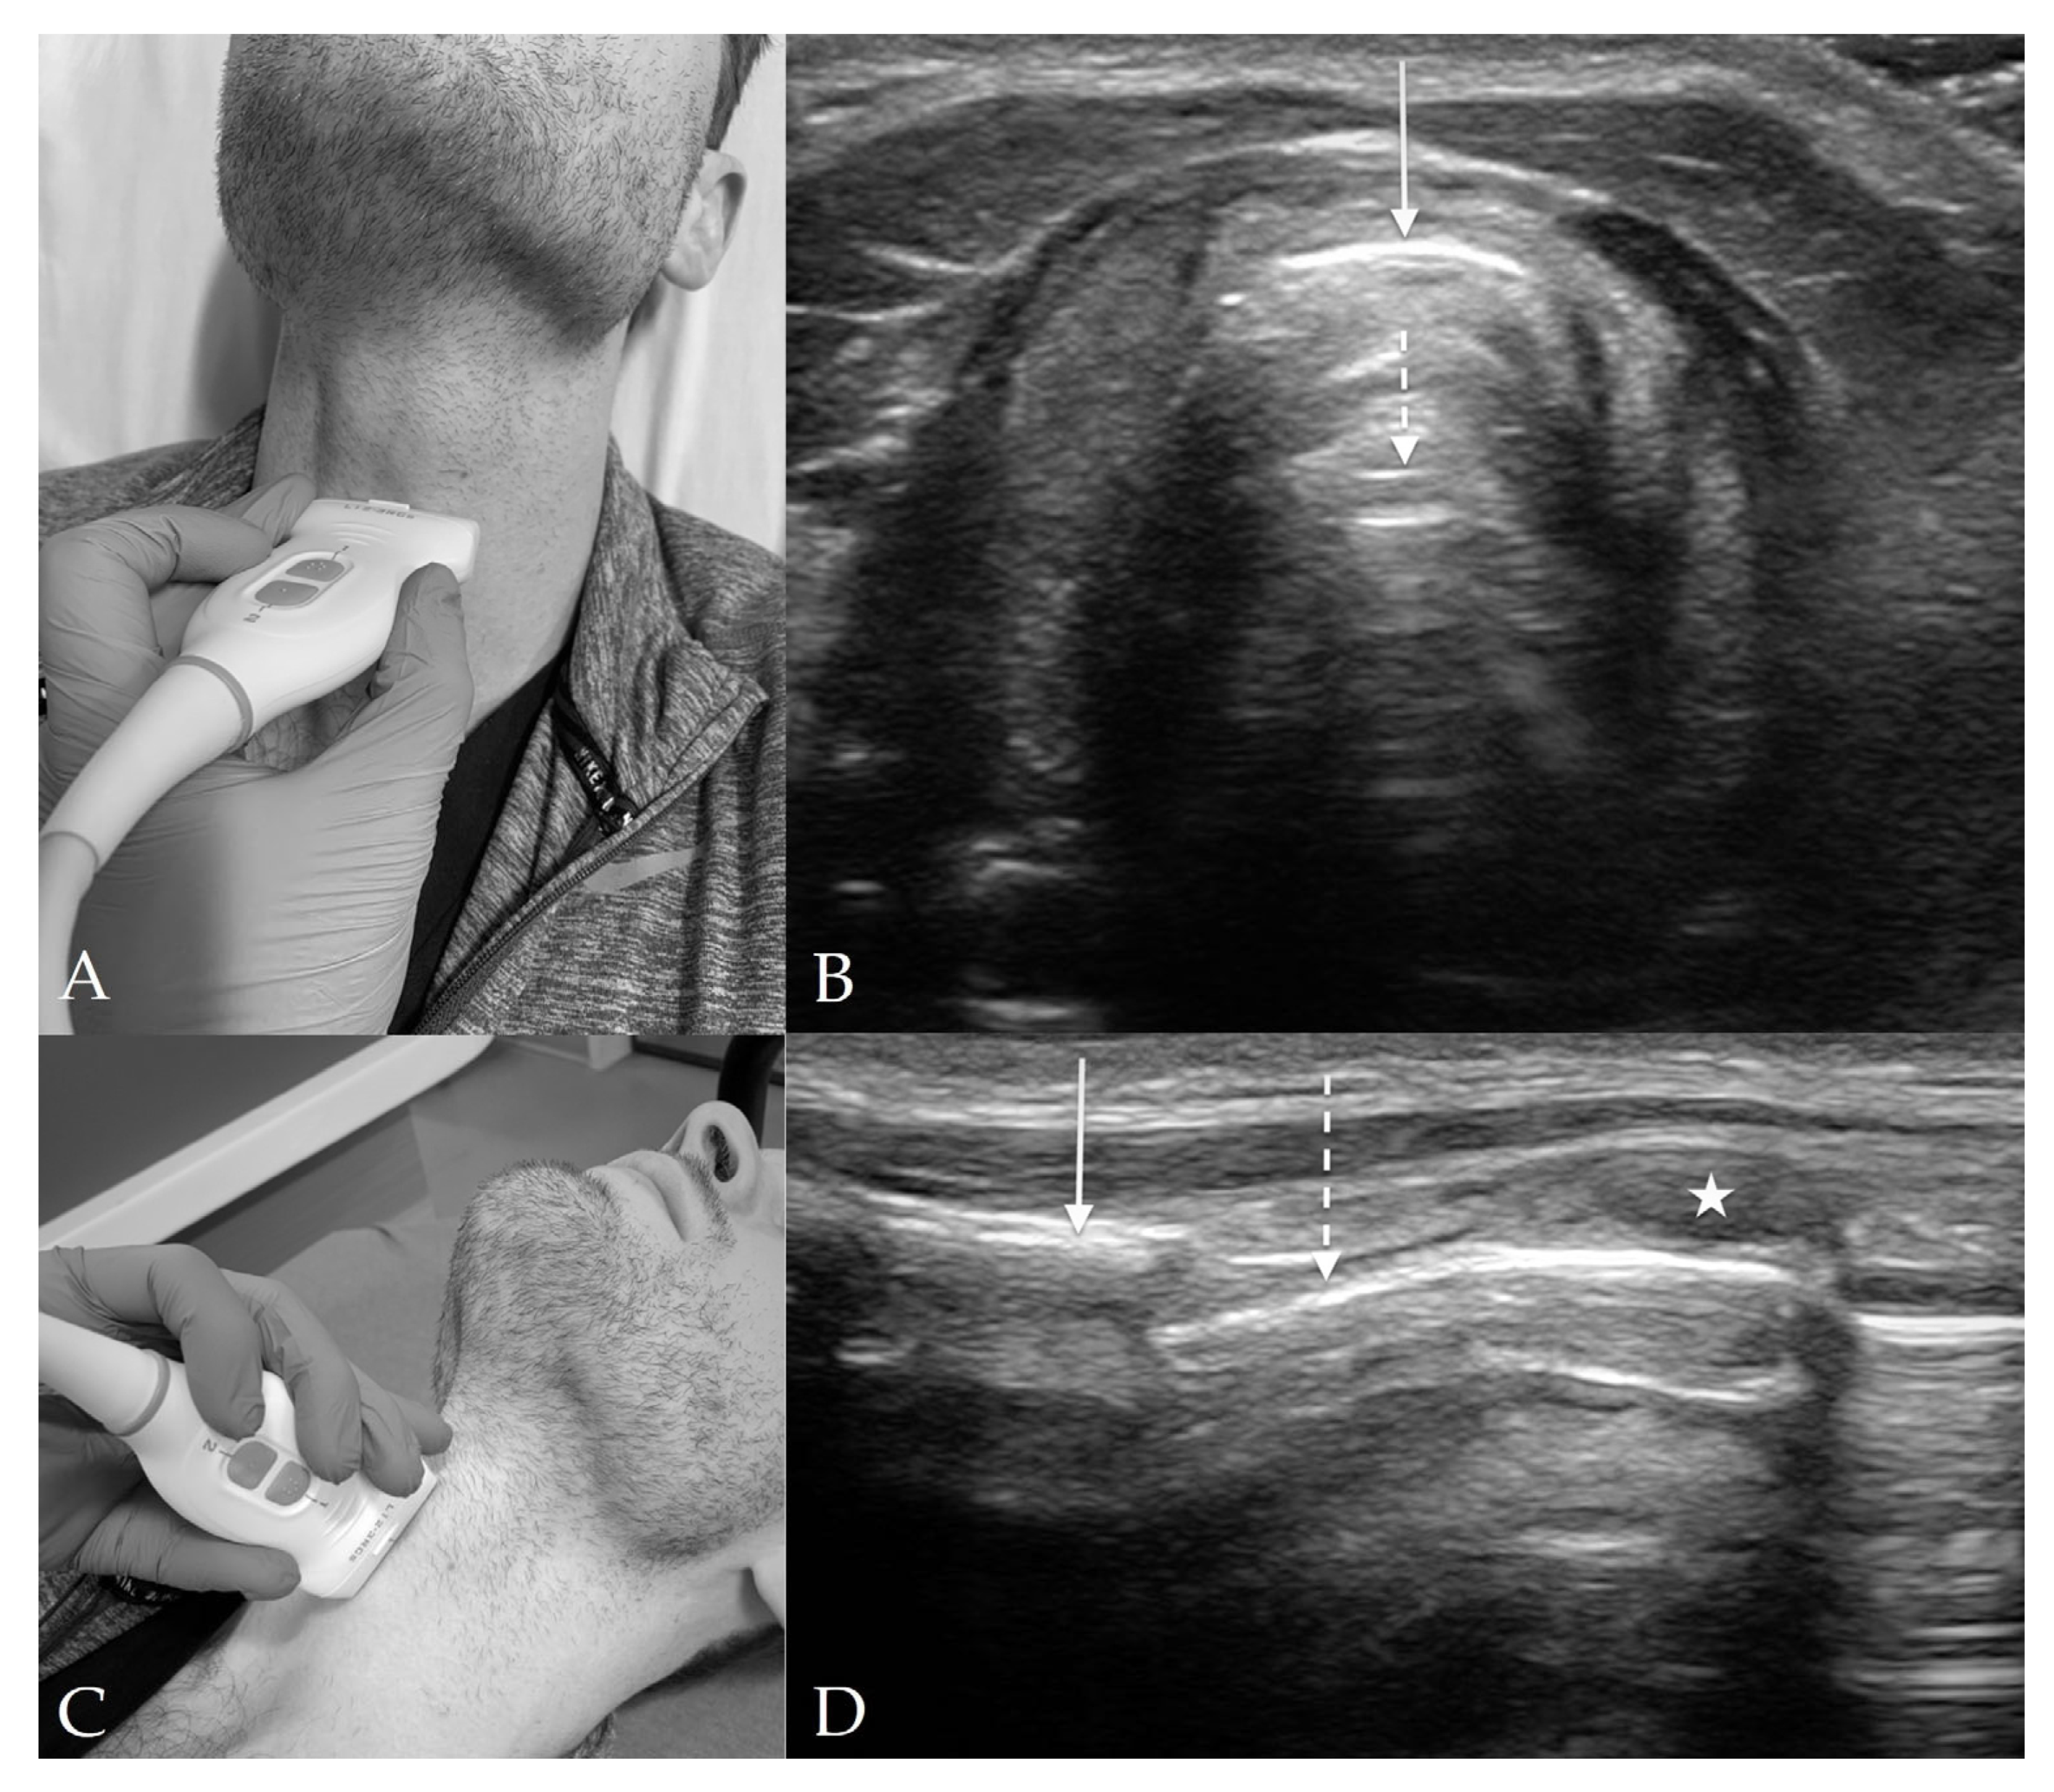

4.4. Cricothyroid View

4.5. Suprasternal View